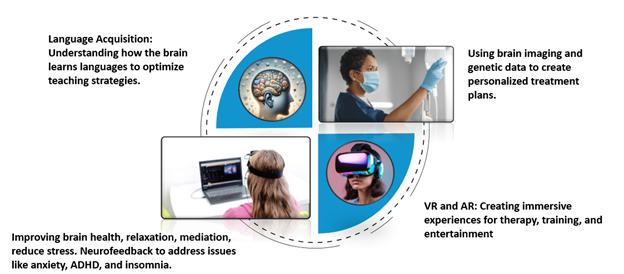

4. Emerging Technologies and Future Directions

Beyond diagnostics, neuroscience is pioneering new modalities for rehabilitation and enhancement:

- Brain–Computer Interfaces (BCIs) and Neurofeedback

Wearable EEG devices combined with real-time feedback enable users to train attention, manage stress, and support recovery after brain injury. - Virtual and Augmented Reality

Immersive environments are being developed for exposure therapy, skill learning, and cognitive rehabilitation, offering controlled, adaptable stimuli that engage neural plasticity. - Personalized Neurotherapies

Integrating brain imaging, genetic profiling, and AI-driven analytics, researchers aim to tailor interventions—whether pharmacological or electromagnetic—to each individual’s unique neural signature.